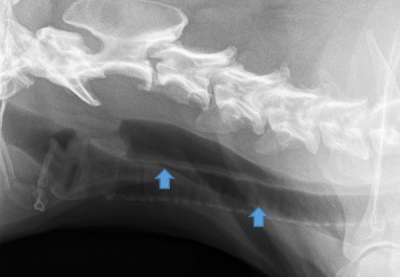

Since April 2014, vets in Latvia have observed a sudden increase in megaesophagus and laryngeal paralysis in dogs. There were over 100 confirmed cases by mid June - and...